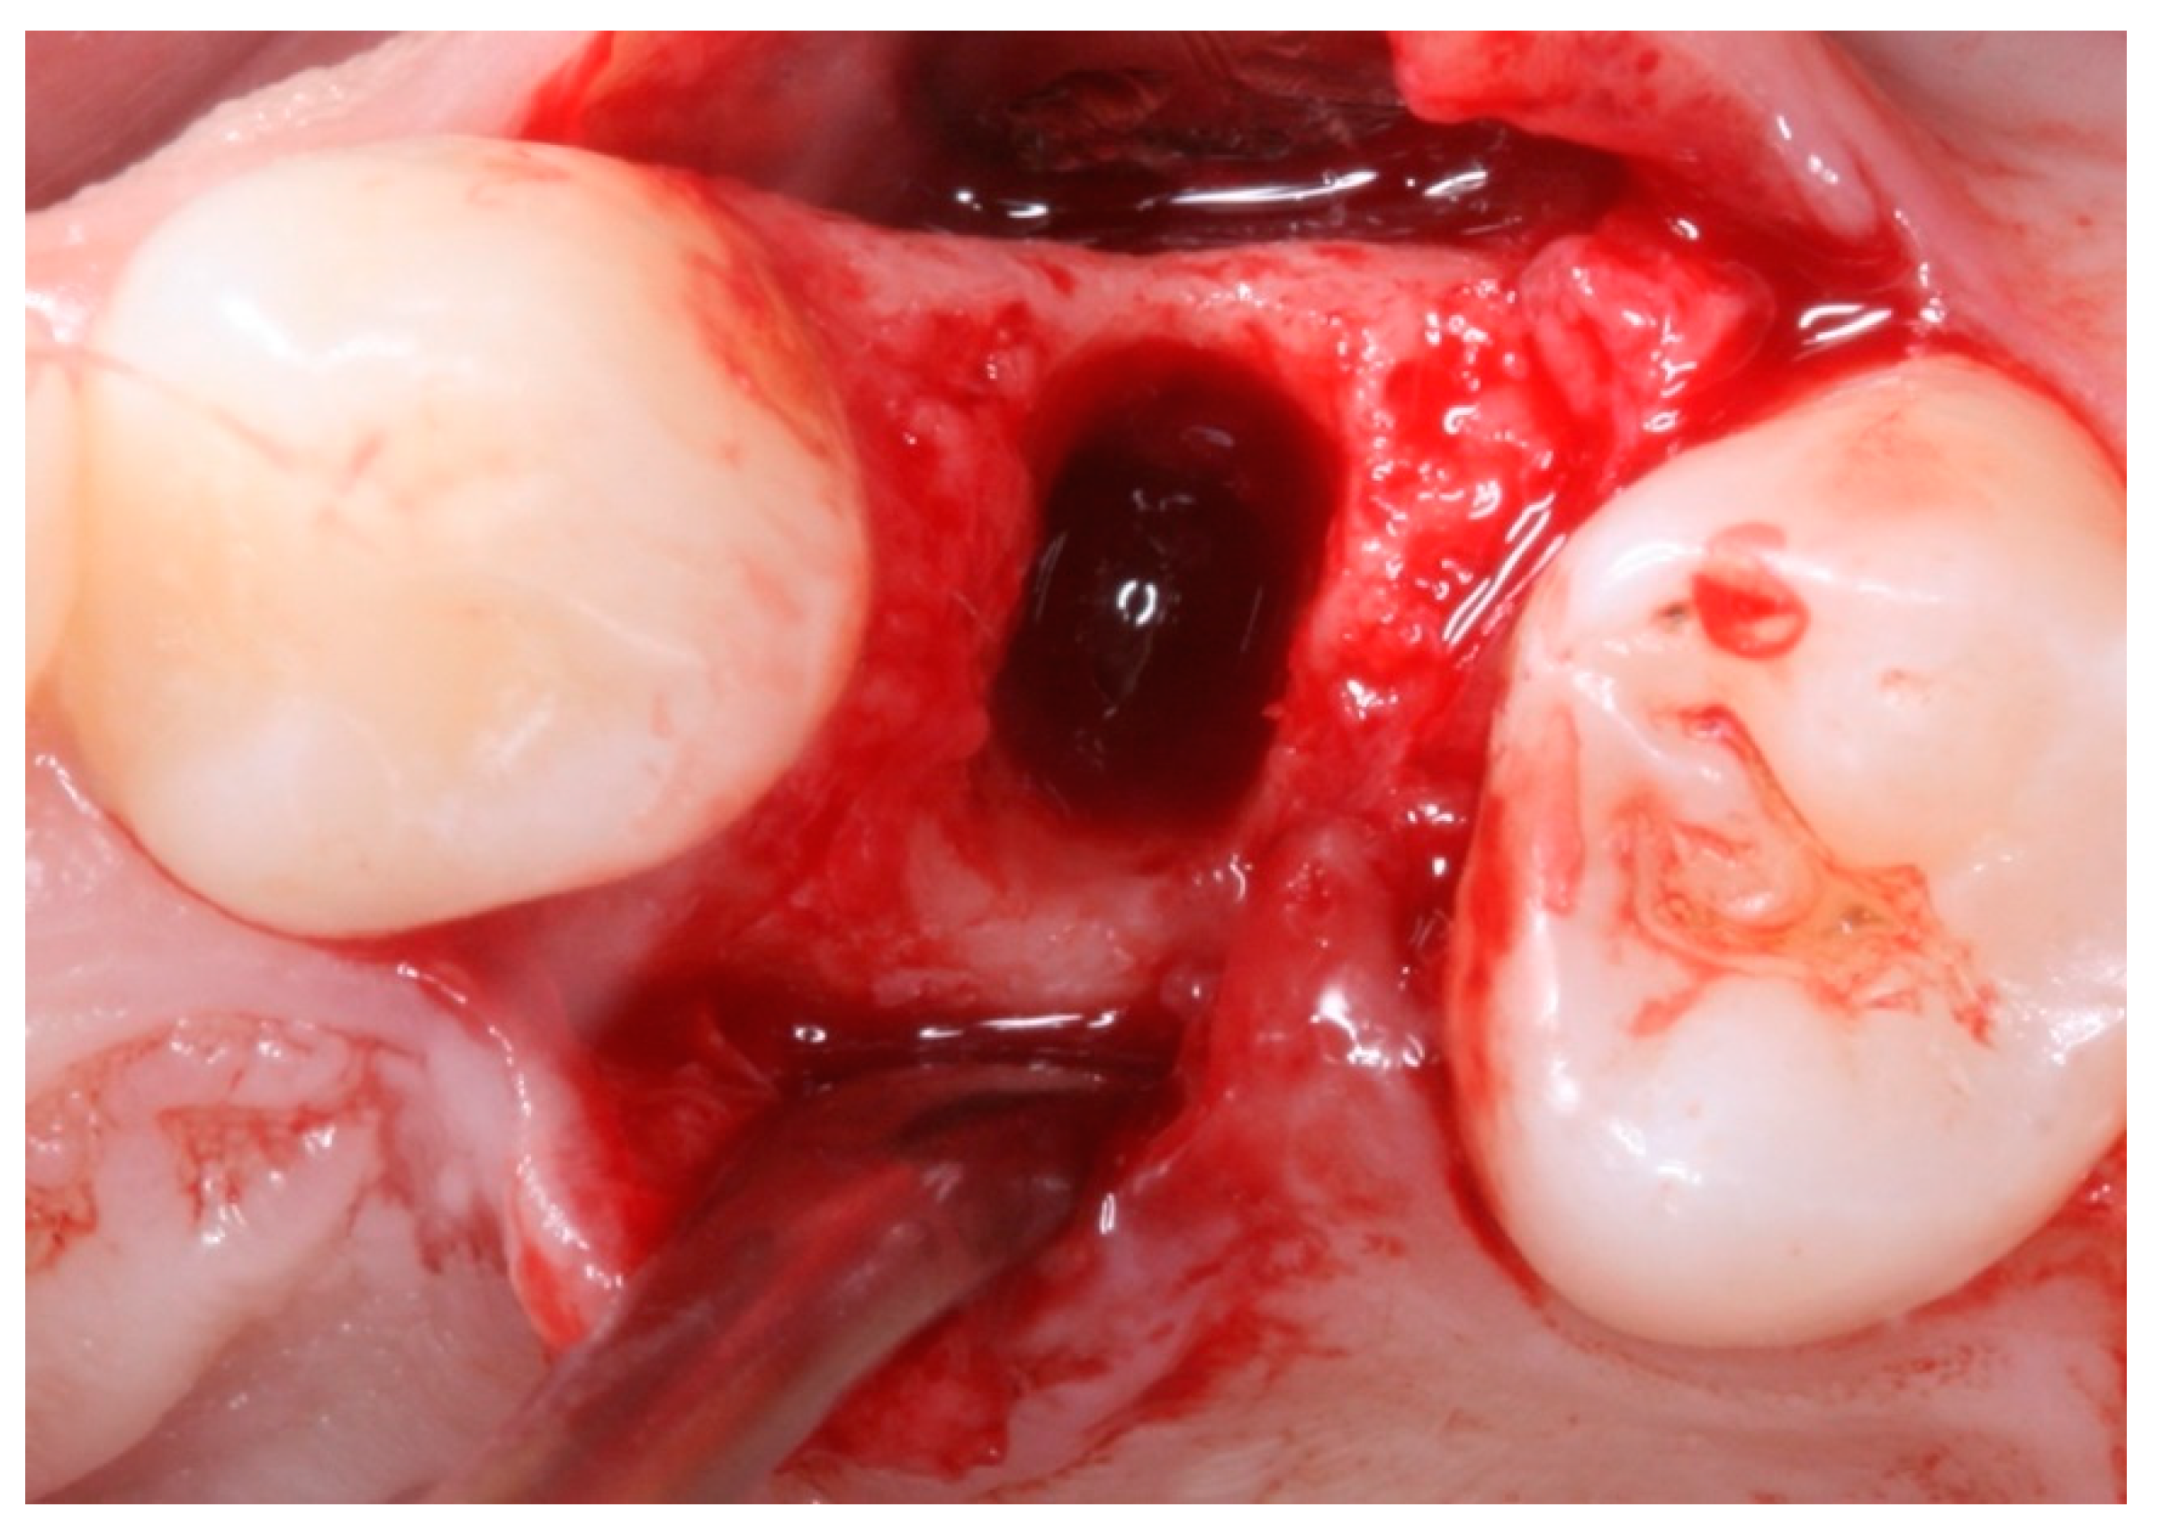

2. Materials and Methods

2.4. Groups